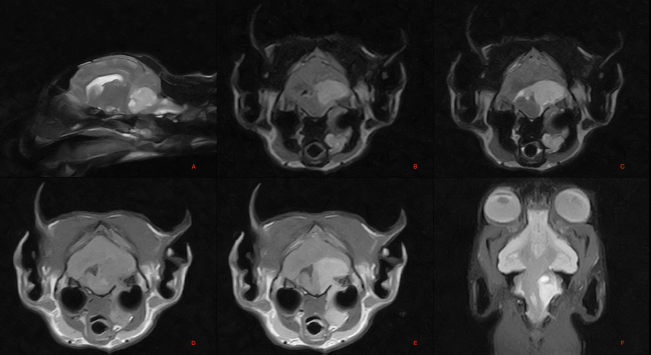

A magnetic resonance study of the skull was then performed (Hitachi Airis II, 0.3T). T2-weighted and T1-weighted scans were performed on the transverse and sagittal planes, sequence of a multiecho gradient recalled echo (GET2*), short tau inversion recovery (STIR), and 3DT1 on the dorsal plane. T1-weighted scans were then acquired after the administration of paramagnetic contrast medium (Gadoteridol, Prohance 279.3 mg/ml, 0.2 ml/kg).

The images showed a voluminous extra-axial lesion, with irregular morphology and defined margins, affecting the region of the left metencephalon, with intracranial extension in the region of the pons, in the rostral portion of the medulla oblongata, in the cerebellar vermis, flocculus, and left cerebellar hemisphere (Fig. 1).

Erosion of the petrous portion of the left temporal bone was observed with extracranial extension and slight dorsal compression of the left tympanic bulla, which appeared slightly deformed. In addition, there was invasion/compression of the left longus colli muscle and digastric muscles.

The lesion signal appeared hyperintense to the brain parenchyma and surrounding musculature and heterogeneous in the T2-weighted, fluid-attenuated inversion recovery (FLAIR), STIR, and GET2* sequences, and isointense in the T1-weighted sequences. Contrast uptake was marked and heterogeneous.

The lesion resulted in compression and right dislocation of the pons, medulla oblongata, cerebellar vermis, and left cerebral hemisphere. It compressed and displaced to the right the mesencephalic aqueduct and rostrolaterally to the left, the left lateral recess of the fourth ventricle, which appeared slightly distended.

There was a slight symmetrical dilation of the entire ventricular system, including the cavities of the olfactory bulbs. Marked perilesional edema was present. The extracranial portion of the lesion caused mass effect and lateral dislocation of the left hemiportion of the hyoid bone.

Fig. 1. Magnetic resonance imaging (MRI) of the skull: T2-weighted images of the brain, parasagittal plane (A), STIR image, transverse plane at the level of the pons (B), T2 weighted image, transverse plane at the level of the pons (C), T1 weighted image, transverse plane at the level of the pons (D), T1 weighted post contrast image, transverse plane at the level of the pons (E). Dorsal Gradient Echo T2* weighted image of the brain, dorsal plane (F). Voluminous extra axial lesion affecting the region of the left metencephalon.